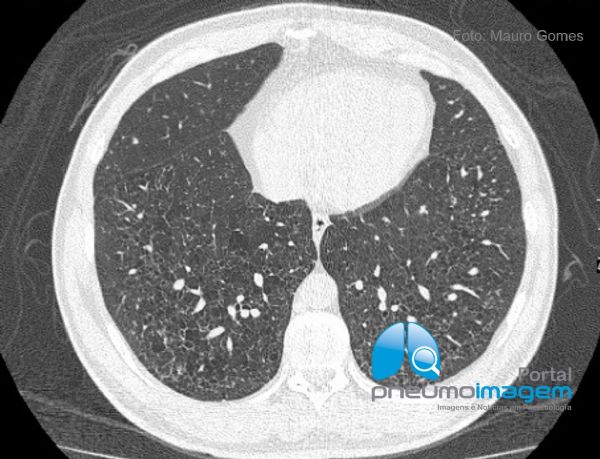

Comprometimento pulmonar da Histiocitose de Células de Langerhans caracterizado por pequenos cistos arredondados de paredes finas, bilaterais, de distribuição difusa e homogênea pelas regiões centrais e periféricas dos pulmões. Ainda há espessamento de septos interlobulares e discretas áreas em vidro fosco.

Pulmonary involvement of Langerhans cell Histiocytosis characterized by small round, thin-walled, bilateral cysts of diffuse and homogeneous distribution through the central and peripheral regions of the lungs. There is still thickening of interlobular septa and discrete ground glass opacities.

O achado mais frequente na Histiocitose de Células de Langherans são os cistos pulmonares, geralmente pequenos, mas que também podem assumir tamanhos variados. Em algumas situações as paredes dos cistos podem ser espessas e irregulares, o que não ocorreu nesse caso. A associação com nódulos pulmonares varia de acordo com a fase de evolução da doença (fases mais precoces) e esse achado auxilia na suspeita diagnóstica.

The most common finding in Langherans cell histiocytosis is pulmonary cysts, usually small but can also assume varying sizes. In some situations the walls of the cysts may be thick and irregular, which did not occur in this case. The association with pulmonary nodules varies according to the stage of evolution of the disease (earlier stages) and this finding helps in the diagnostic suspicion.